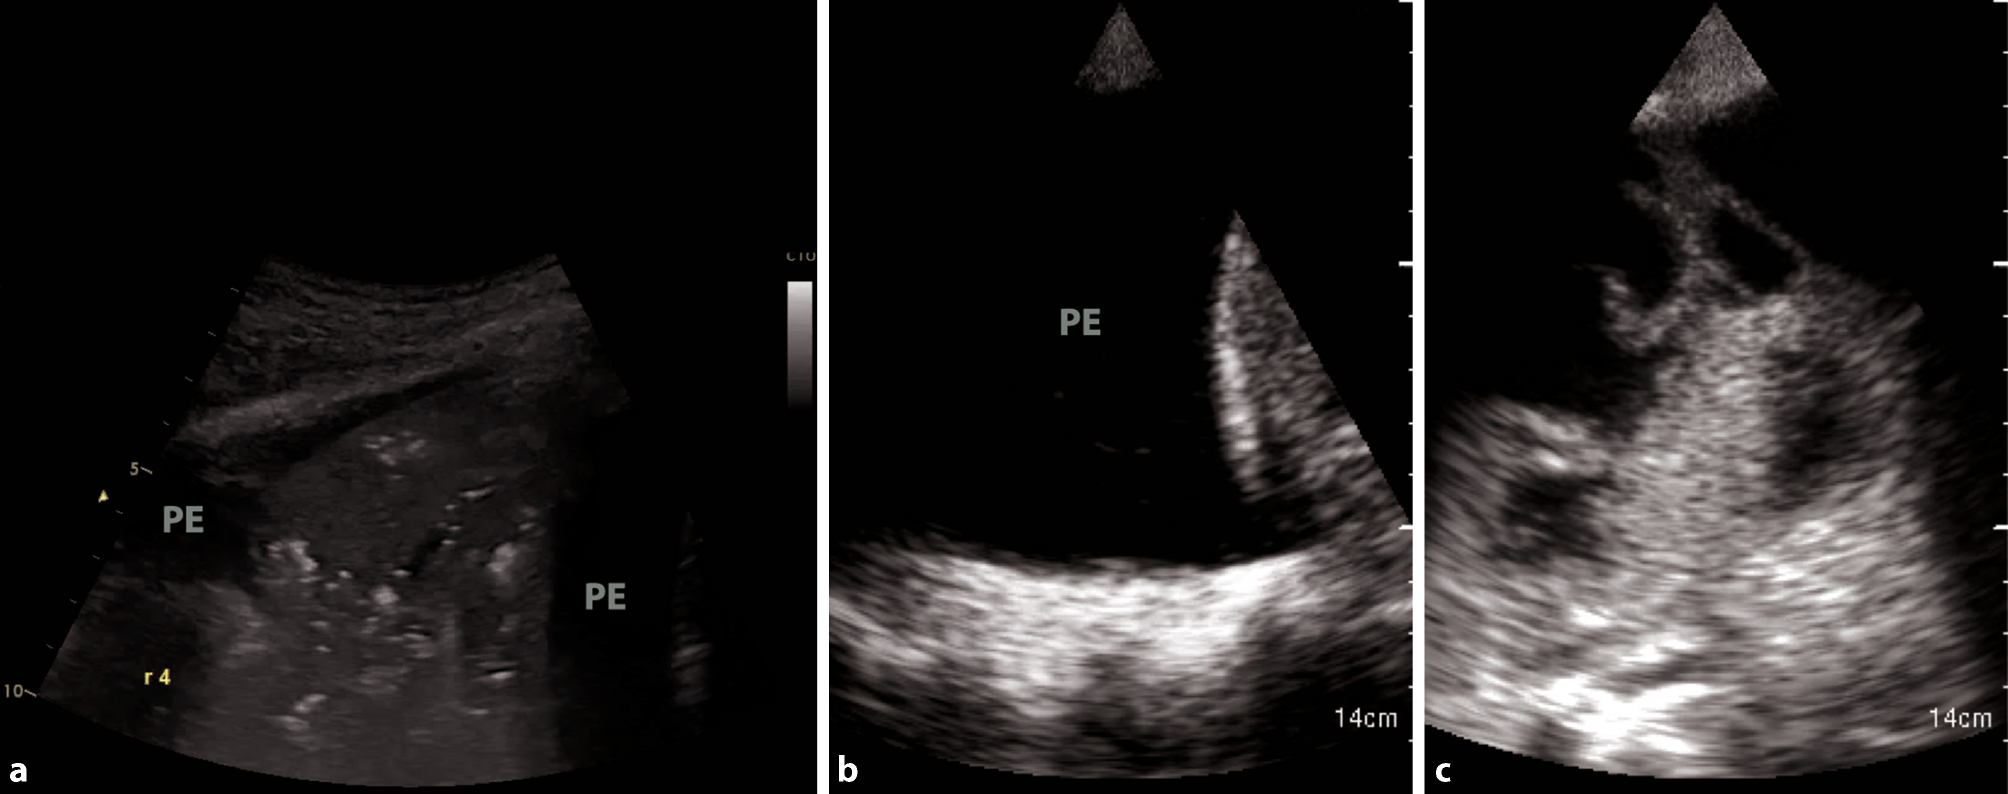

Fig. 4

Different types of pleural effusion. a Consolidation with tissue-like appearance in pneumonia. PE pleural effusion. b Large, uncomplicated pleural effusion in heart failure. c Complicated pleural effusion, empyema

Overall, pleural effusions in the context of bacterial superinfections tend to be small and localized in patients with COVID-19 [28]. If large pleural effusions are present, other differential diagnoses, such as heart failure (in particular right ventricular failure), kidney failure, and liver cirrhosis, have to be considered (Fig. 4b; [38]).

POCUS has been demonstrated to be a valuable tool to diagnose complications of COVID-19, such as pneumothorax or pleural effusions, or to confirm the suspected complications such as bacterial superinfections (Fig. 4a, c).

Pleural effusions are reportedly rare in COVID-19 pneumonia, and thus indicate a bacterial superinfection or heart failure [26]. To detect pleural effusions in supine patients, e.g. in an ICU, we recommend scanning the posterior regions with a convex or cardiac transducer as posterior as possible (Figs. 9 and 10). In an upright patient, the posterior regions—zone six (Fig. 8)—can be visualized with a convex or cardiac transducer to identify pleural effusions. In large pleural effusions, compression atelectasis can be visualized. Likewise, as previously mentioned, differential diagnoses of pleural effusions have to be considered [39]. The suspicion of heart failure is further supported by the presence of reverberation artifacts, which arise from a non-fragmented pleural line (B-lines). These B‑lines arise from the smooth pleural line in a bilateral homogenous way, not fading until the end of the screen, moving with pleural sliding and erasing other artifacts (A-lines). The presence and quantity of B‑lines correlate with the severity of clinical presentation of patients [24, 35, 40].